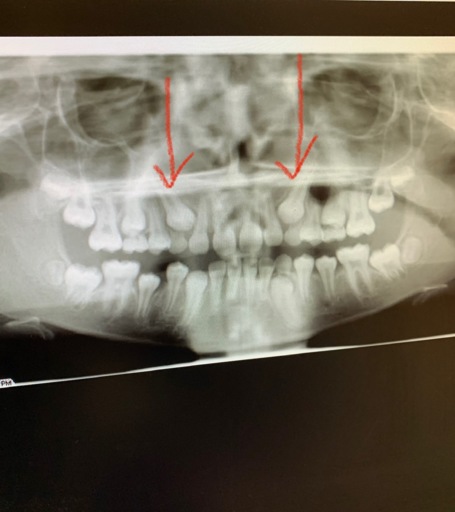

Impacted Canines

What is the procedure for impacted Canines that are at the top only for both canines and they are in the top of the gums on the outside (not in palette). I have an X-ray. ITS FOR MY DAUGHTER... 12 years old and 2 months.